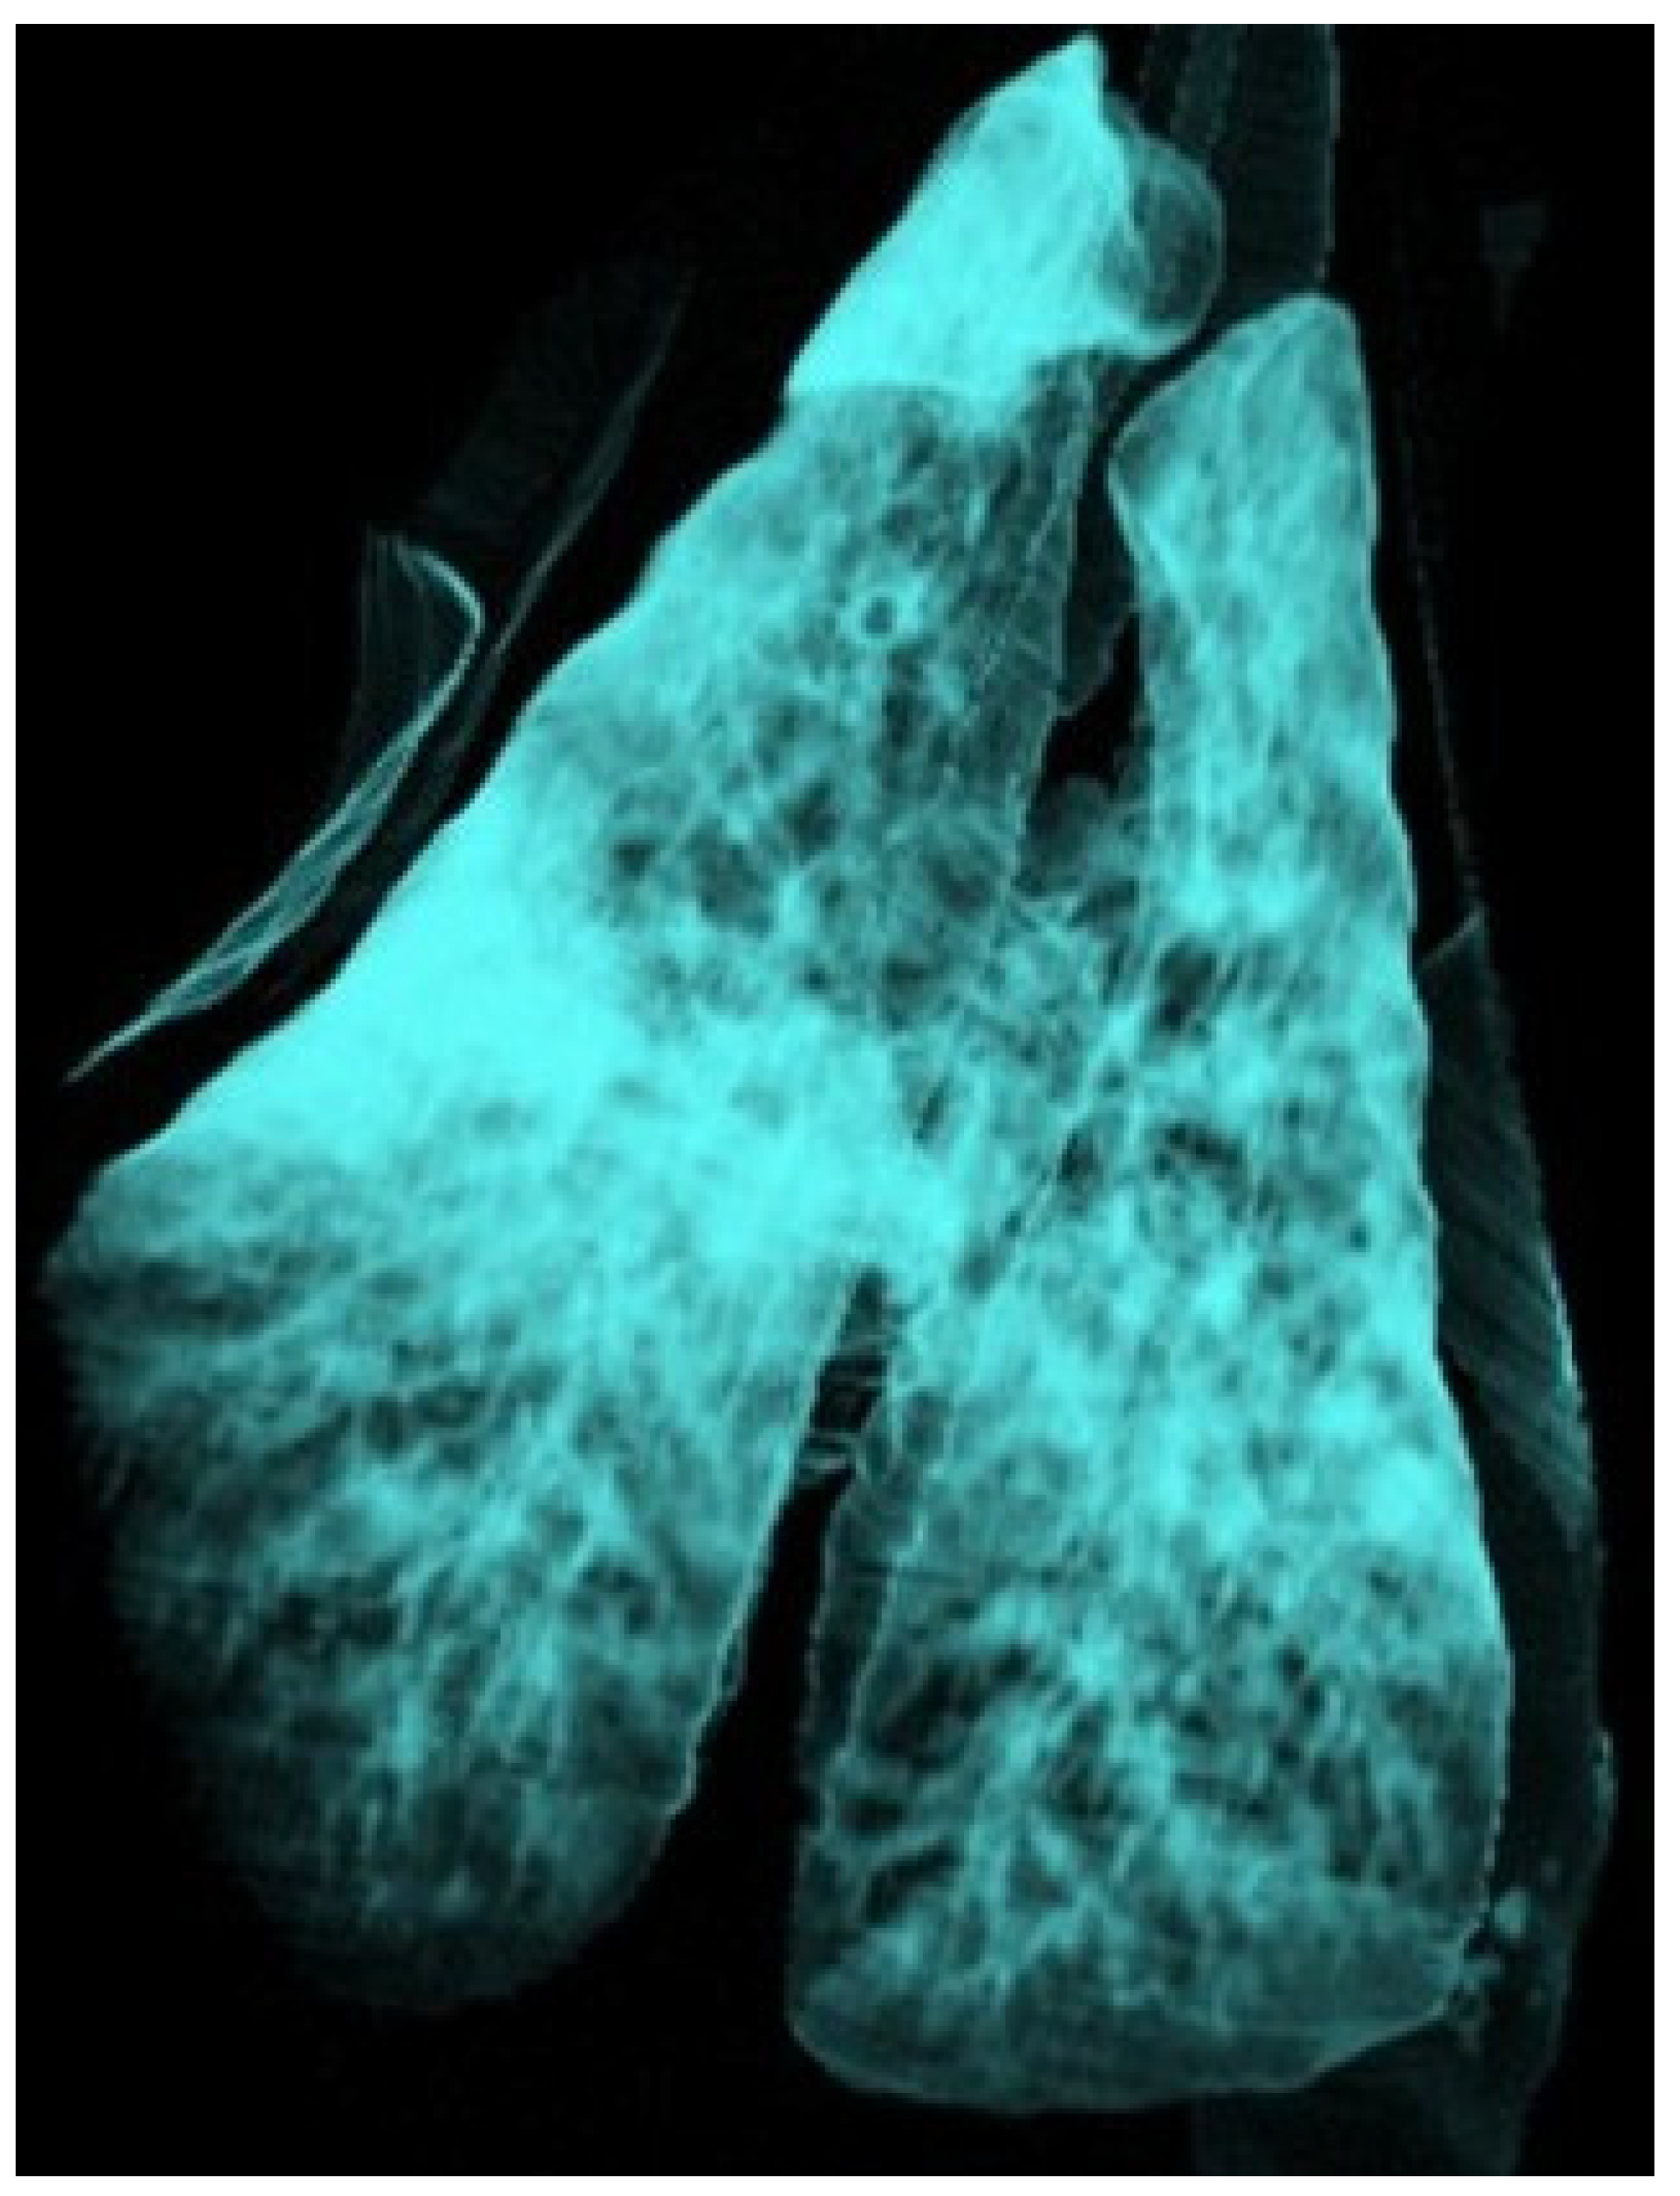

3.3.6. Ovine Pulmonary Adenocarcinoma (OPA)

| OPA | Primary masses with satellite nodules | −5 to −30 HU (primary), −90 to −200 HU (metastases) | Solid masses; differences in tissue composition between primary and metastatic lesions |